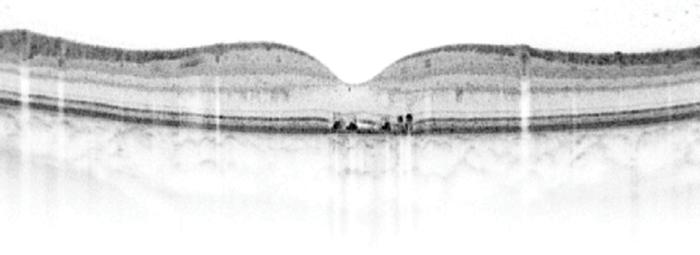

Figure 2: Spectral Domain OCT of same patient showing permanent sub-foveal

outer retinal layer disruption with associated visual loss.